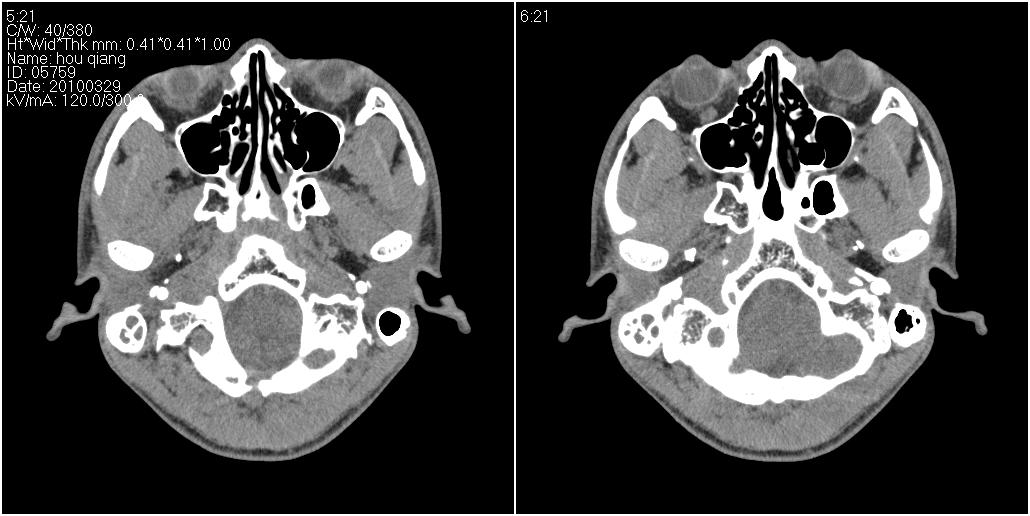

标题: CT25419:男性,18岁。右耳肿、痛5个多月。 [打印本页]

标题: CT25419:男性,18岁。右耳肿、痛5个多月。

右侧中耳乳突炎累及外耳道,鼻咽腺样体肥大。

1)右侧慢性中耳乳突炎并右侧中耳腔及外耳道肉芽肿或胆脂瘤形成。2)鼻咽腺样体肥大。